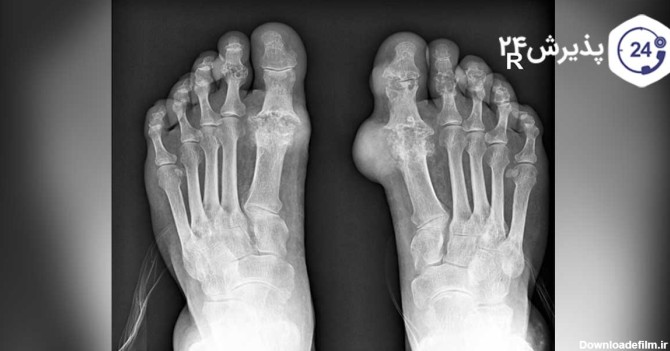

عکس نقرس مچ پا

نقرس چیست، علت ایجاد نقرس،نحوه تشخیص،درمان به وسیله دارو، روش های پیشگیری از ابتلاء و چه غذاهایی برای کسانی که نقرس دارند مفید است یا ضرر دارد

نقرس مچ پا در اکثر موارد غیر قابل پیش بینی است و شما بدون اطلاع از این که کدام مفصل را درگیر کرده، ممکن است دچار این عارضه شده باشید.